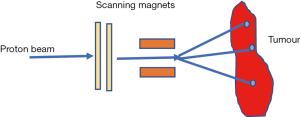

In PBS nozzle, a sharp pencil beam of protons is deflected over x-y directions using magnetic fields (10,14,18,19). Every beam has a finite beam spot size (typically millimetres in dimensions) with fluence that is Gaussian distributed. The beam is swept laterally orthogonal to the beam direction. To create dose deposition at varying depth of the target, the proton beam energy is changed while maintaining the lateral scanning. A superposition of all the pencil beams therefore creates a 3-D dose distribution (Figure 6).